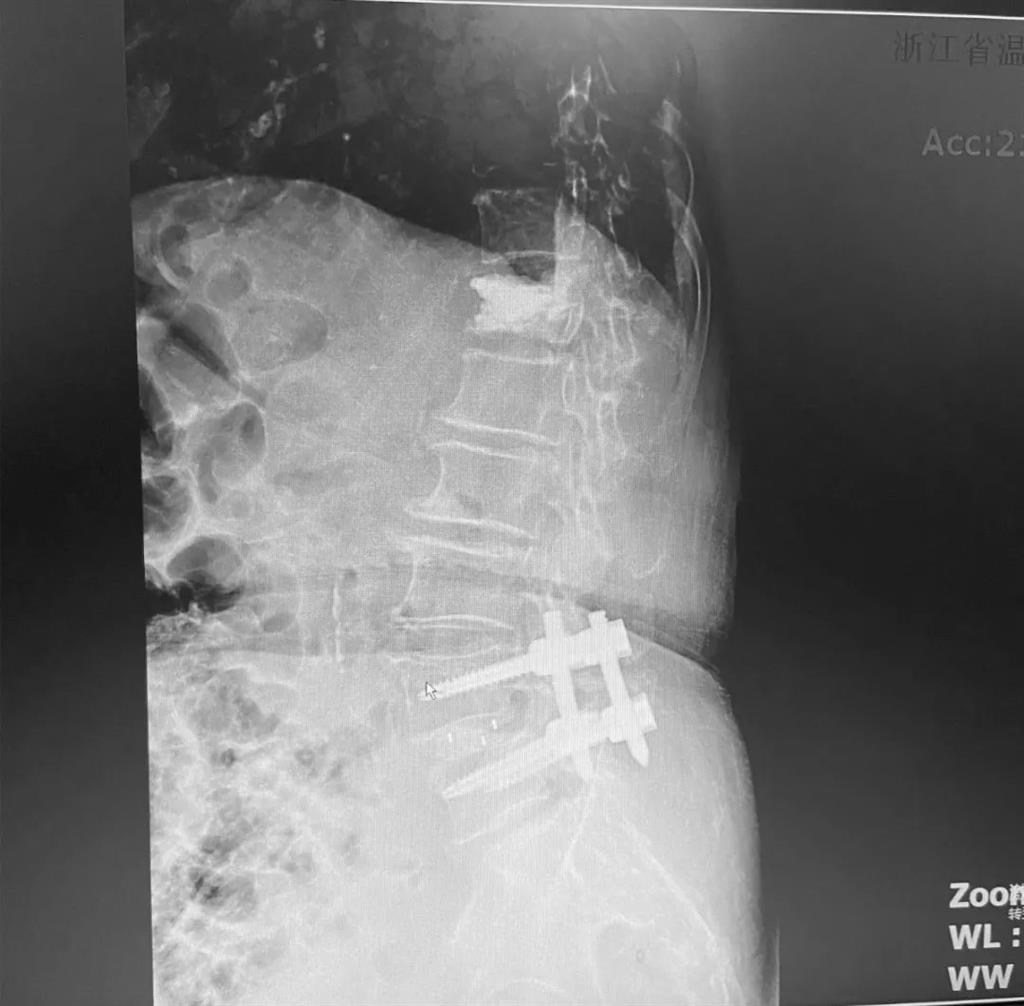

據了解,脊柱內鏡下腰椎融合術只需要打幾個“鑰匙孔”即可完成。聽起來是不是很簡單?在脊柱內鏡下,劉丹主任先后為患者進行了椎管減壓、椎間盤摘除,再實施椎弓根螺釘放置、椎體植骨融合內固定,一系列步驟有條不紊。

術中只需切開4個如“鑰匙孔”般大小的孔道